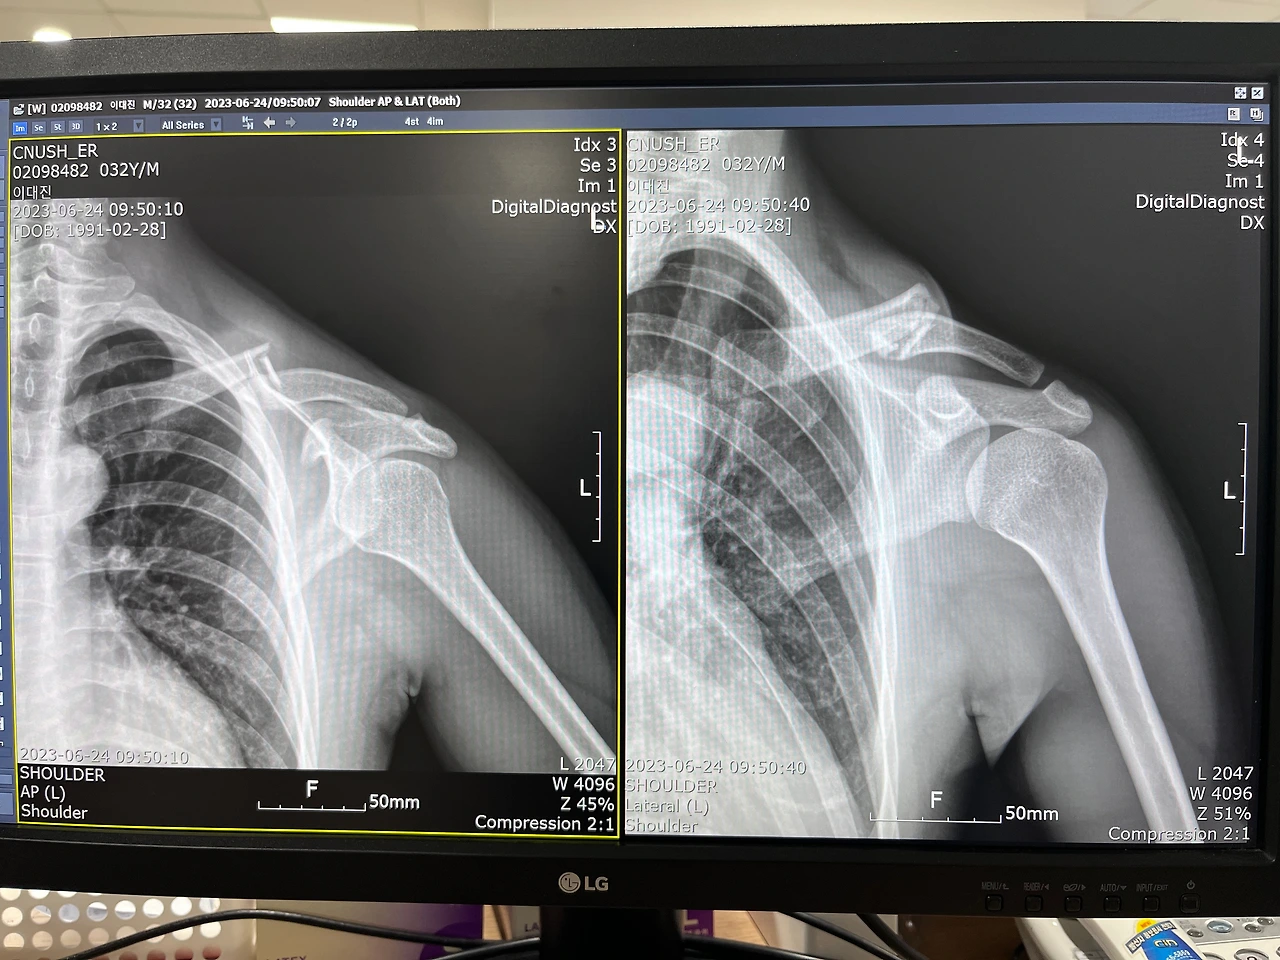

낙차 순간은 기억이 안 나는데 왼쪽으로 굴렀다는 것만 얼핏 스쳐 지나간다. 구급차에 실려 병원에 가서 사진을 찍어보니 골절이었다. 그제야 통증이 밀려든다.